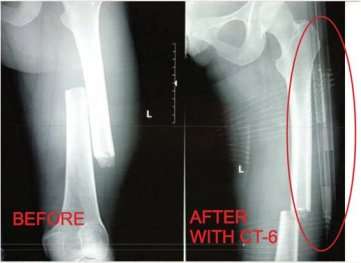

CT-6 Tractie Splint

De CT6 Tractie Splint is al meer dan 20 jaar op de markt en is door de jaren heen gemoderniseerd, voorzien van verbeterde materialen en lichter en kleiner gemaakt. De CT6 geeft pijnverlichting bij een femurfractuur en voorkomt onnodige weefselschade, het evacueren (patientmovement) is daarmee ook een stuk draaglijker. In militaire setting is de CT6 geregeld gebruikt om bovenbenen gecontroleerd "te zetten" bij een femurfractuur.

Carbon Fiber Tubing, corrosiebestendig, temperatuurstabiel, extreem hoge sterkte-gewichtsverhouding, röntgendoorlatend.